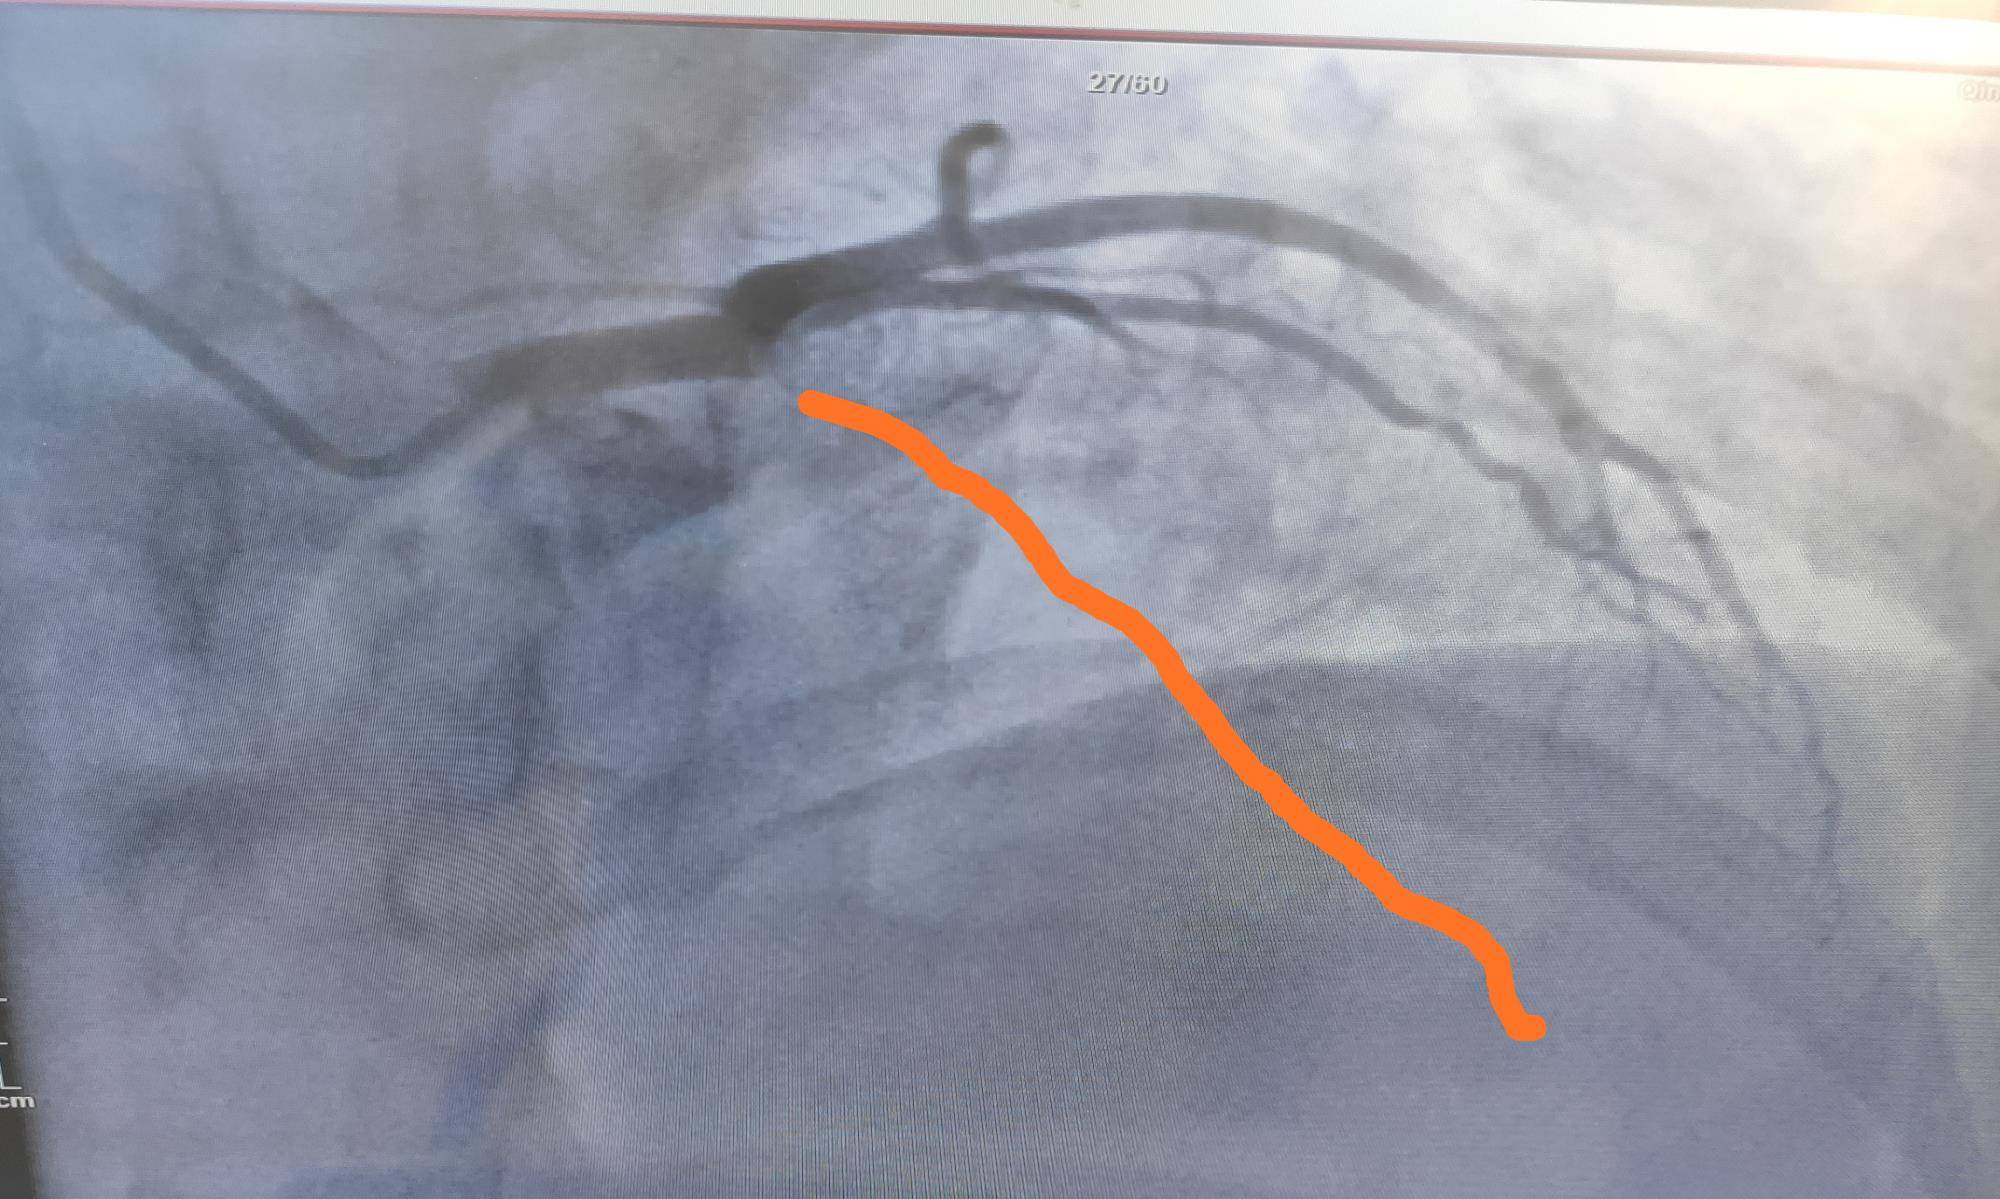

造影结果显示:左主干通畅 , 前降支开口100%闭塞 , 可见回旋支向前降支远段发出侧支循环 。 右冠近段、远段斑块 。 可见右冠向前降支发出侧支循环 。 最终在前降支出放了1枚支架 。